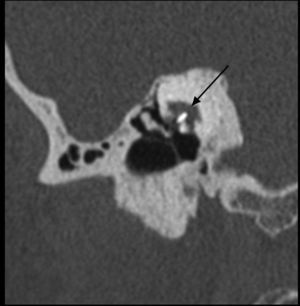

Graduación por TC de la otoesclerosis. Clasificación de Symons y Fanning13 para graduar el compromiso de la otoesclerosis. Grado 0: Normal. Grado 1: Solo compromiso fenestral. Grado 2: Compromiso coclear parcheado (2a: giro basal; 2b: ápice/giro medio; 2c: giro basal y ápice/giro medio). Grado 3: Compromiso coclear difuso. Todas las imágenes corresponden a cortes axiales de oído derecho en el nivel de la cóclea. Las cabezas de flecha señalan las áreas de hueso espongiótico.

Para la descripción de la ubicación y extensión de las placas de otoespongiosis, en el año 2005 Symons y Fanning proponen un sistema de graduación basado en la distribución de la desmineralización ósea de la cápsula ótica13, que complementa la clasificación propuesta por Rotteveel et al el año 200414. Esta nueva clasificación hace énfasis en la diferencia pronóstica dada por la presencia de focos aislados de otoespongiosis versus compromiso difuso por la enfermedad, siendo aplicada para las formas fenestral y retrofenestral. Otro elemento importante es que esta clasificación ha demostrado tener buena concordancia intra- e interobservador, lo cual fortalece su aplicación en la práctica clínica3. Se resume la clasificación en la tabla 3, y se presentan ejemplos de los distintos grados en la figura 1.